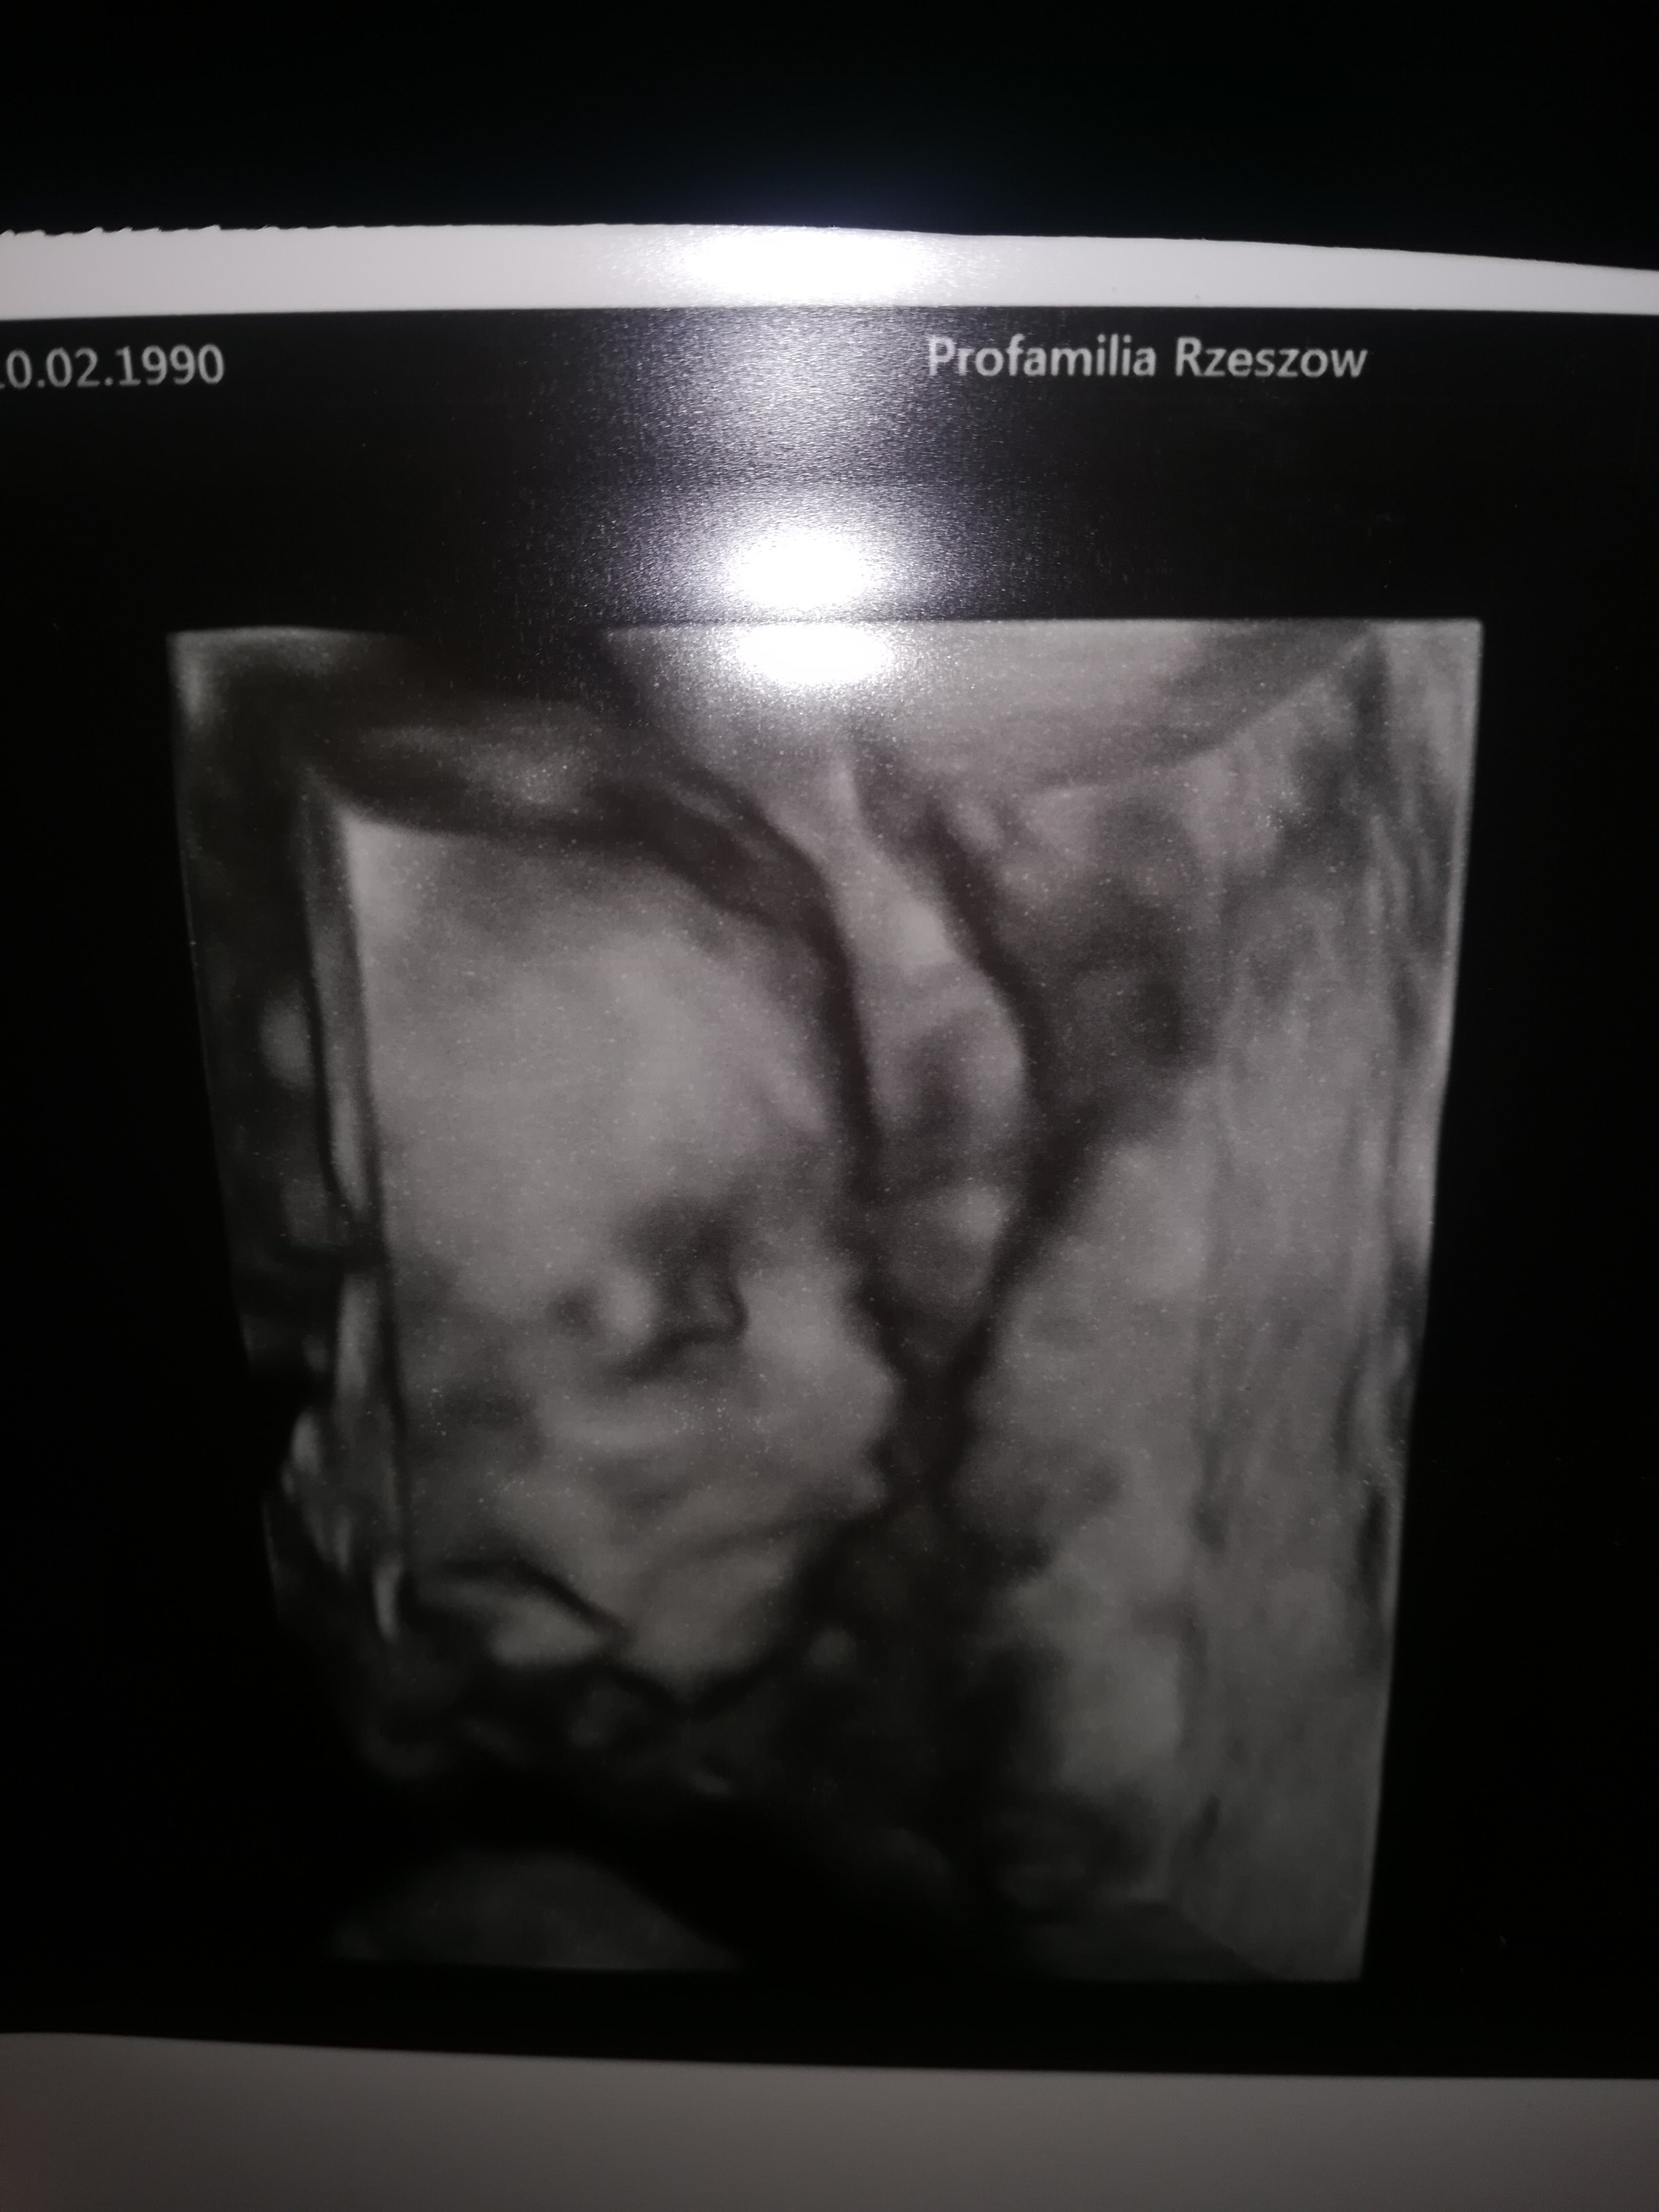

Połówkowe w poniedziałek 03.12 ☺ wszystko w porządku jednak w NL niewiele mówią mamy z mężem teraz wątpliwości bo przy prenatalnych wyszło że będzie chłopak teraz że dziewczynka a jeśli chodzi o mnie to ja nie widzę nic na tym zdjęciu Mamuśki może Wy się wypowiecie?;) a do wstawiam w załączniku

• 20181205_120533.jpg

20181205_120533.jpg

405,4 KB · Wyświetleń: 343